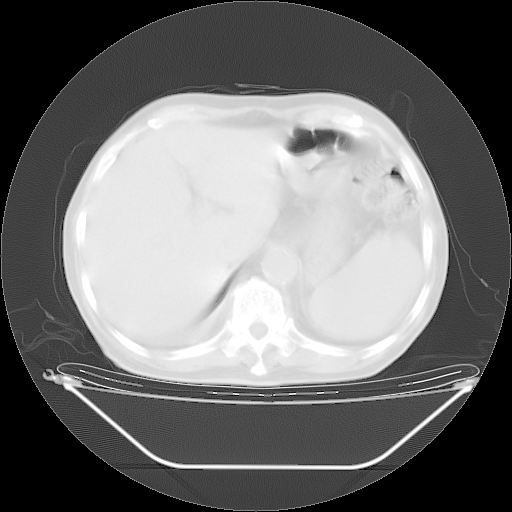

胸腹部CT,诊断意见:左上肺叶钙化灶、左侧胸膜局限性增厚并钙化、胆囊炎。描述部分肺组织呈磨玻璃样改变。

今天复查肺部CT,发现双肺广泛磨玻璃样改变。所以我把3月19日和5月9日相隔50天的肺部CT上传。请大家会诊。

5月9日肺部CT(在4月27日齐鲁医院肺部CT描述部分肺组织磨玻璃样改变,12天后肺组织广泛磨玻璃样改变)

大致读了系列胸部CT:纵隔窗无明显异常,肺窗:从4、27至今:主要是双肺中下野外带可见毛玻璃样改变,目前处于急性肺泡炎阶段,至于原因考虑1、结替组织或胶原血管性疾病所致?2、恶性疾病如恶组在肺部所致的表现或细支气管肺泡癌?3、药物或其它原因如肺蛋白沉着症所致肺泡炎目前不太可能?总之,明天就去请我院的呼吸科、感染科、血液科和临免专家会诊哈。